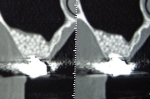

ガイド使用フラップレス骨移植インプラント同時症例

通常これほど骨が薄い場合は上の症例の様な大きな骨の移植が必要となりますが、シュミレーションソフトを使い審査したところギリギリでインプラント埋入と同時に骨の移植を行えると判断。

またシュミレーションを基に作成したインプラント手術ガイドを使用したので歯茎を切らないフラップレスで手術を行うことができました。

フラップレス手術はよくありますが実際は精度が悪くなり術後の歯茎の退縮も起こりやすいので状態が良くないと行わないですが、痛みも少なく患者さんに優しい方法です。

また骨の移植もインプラント埋入の為に開けた穴から空洞内の粘膜を剥がしスペースに移植する方法でこちらも難度が高く半数以上の症例で失敗している(少しの失敗では一部インプラントと結合するので失敗の及ぼす影響はわかりにくいです)という統計データも存在しますが、こちらも術後の痛みも少なく治療期間も大きな移植と比較して6か月程度短縮することができます。

当院では術後にCT撮影を行い結果をごまかさずに患者さんと一緒に確認しています。